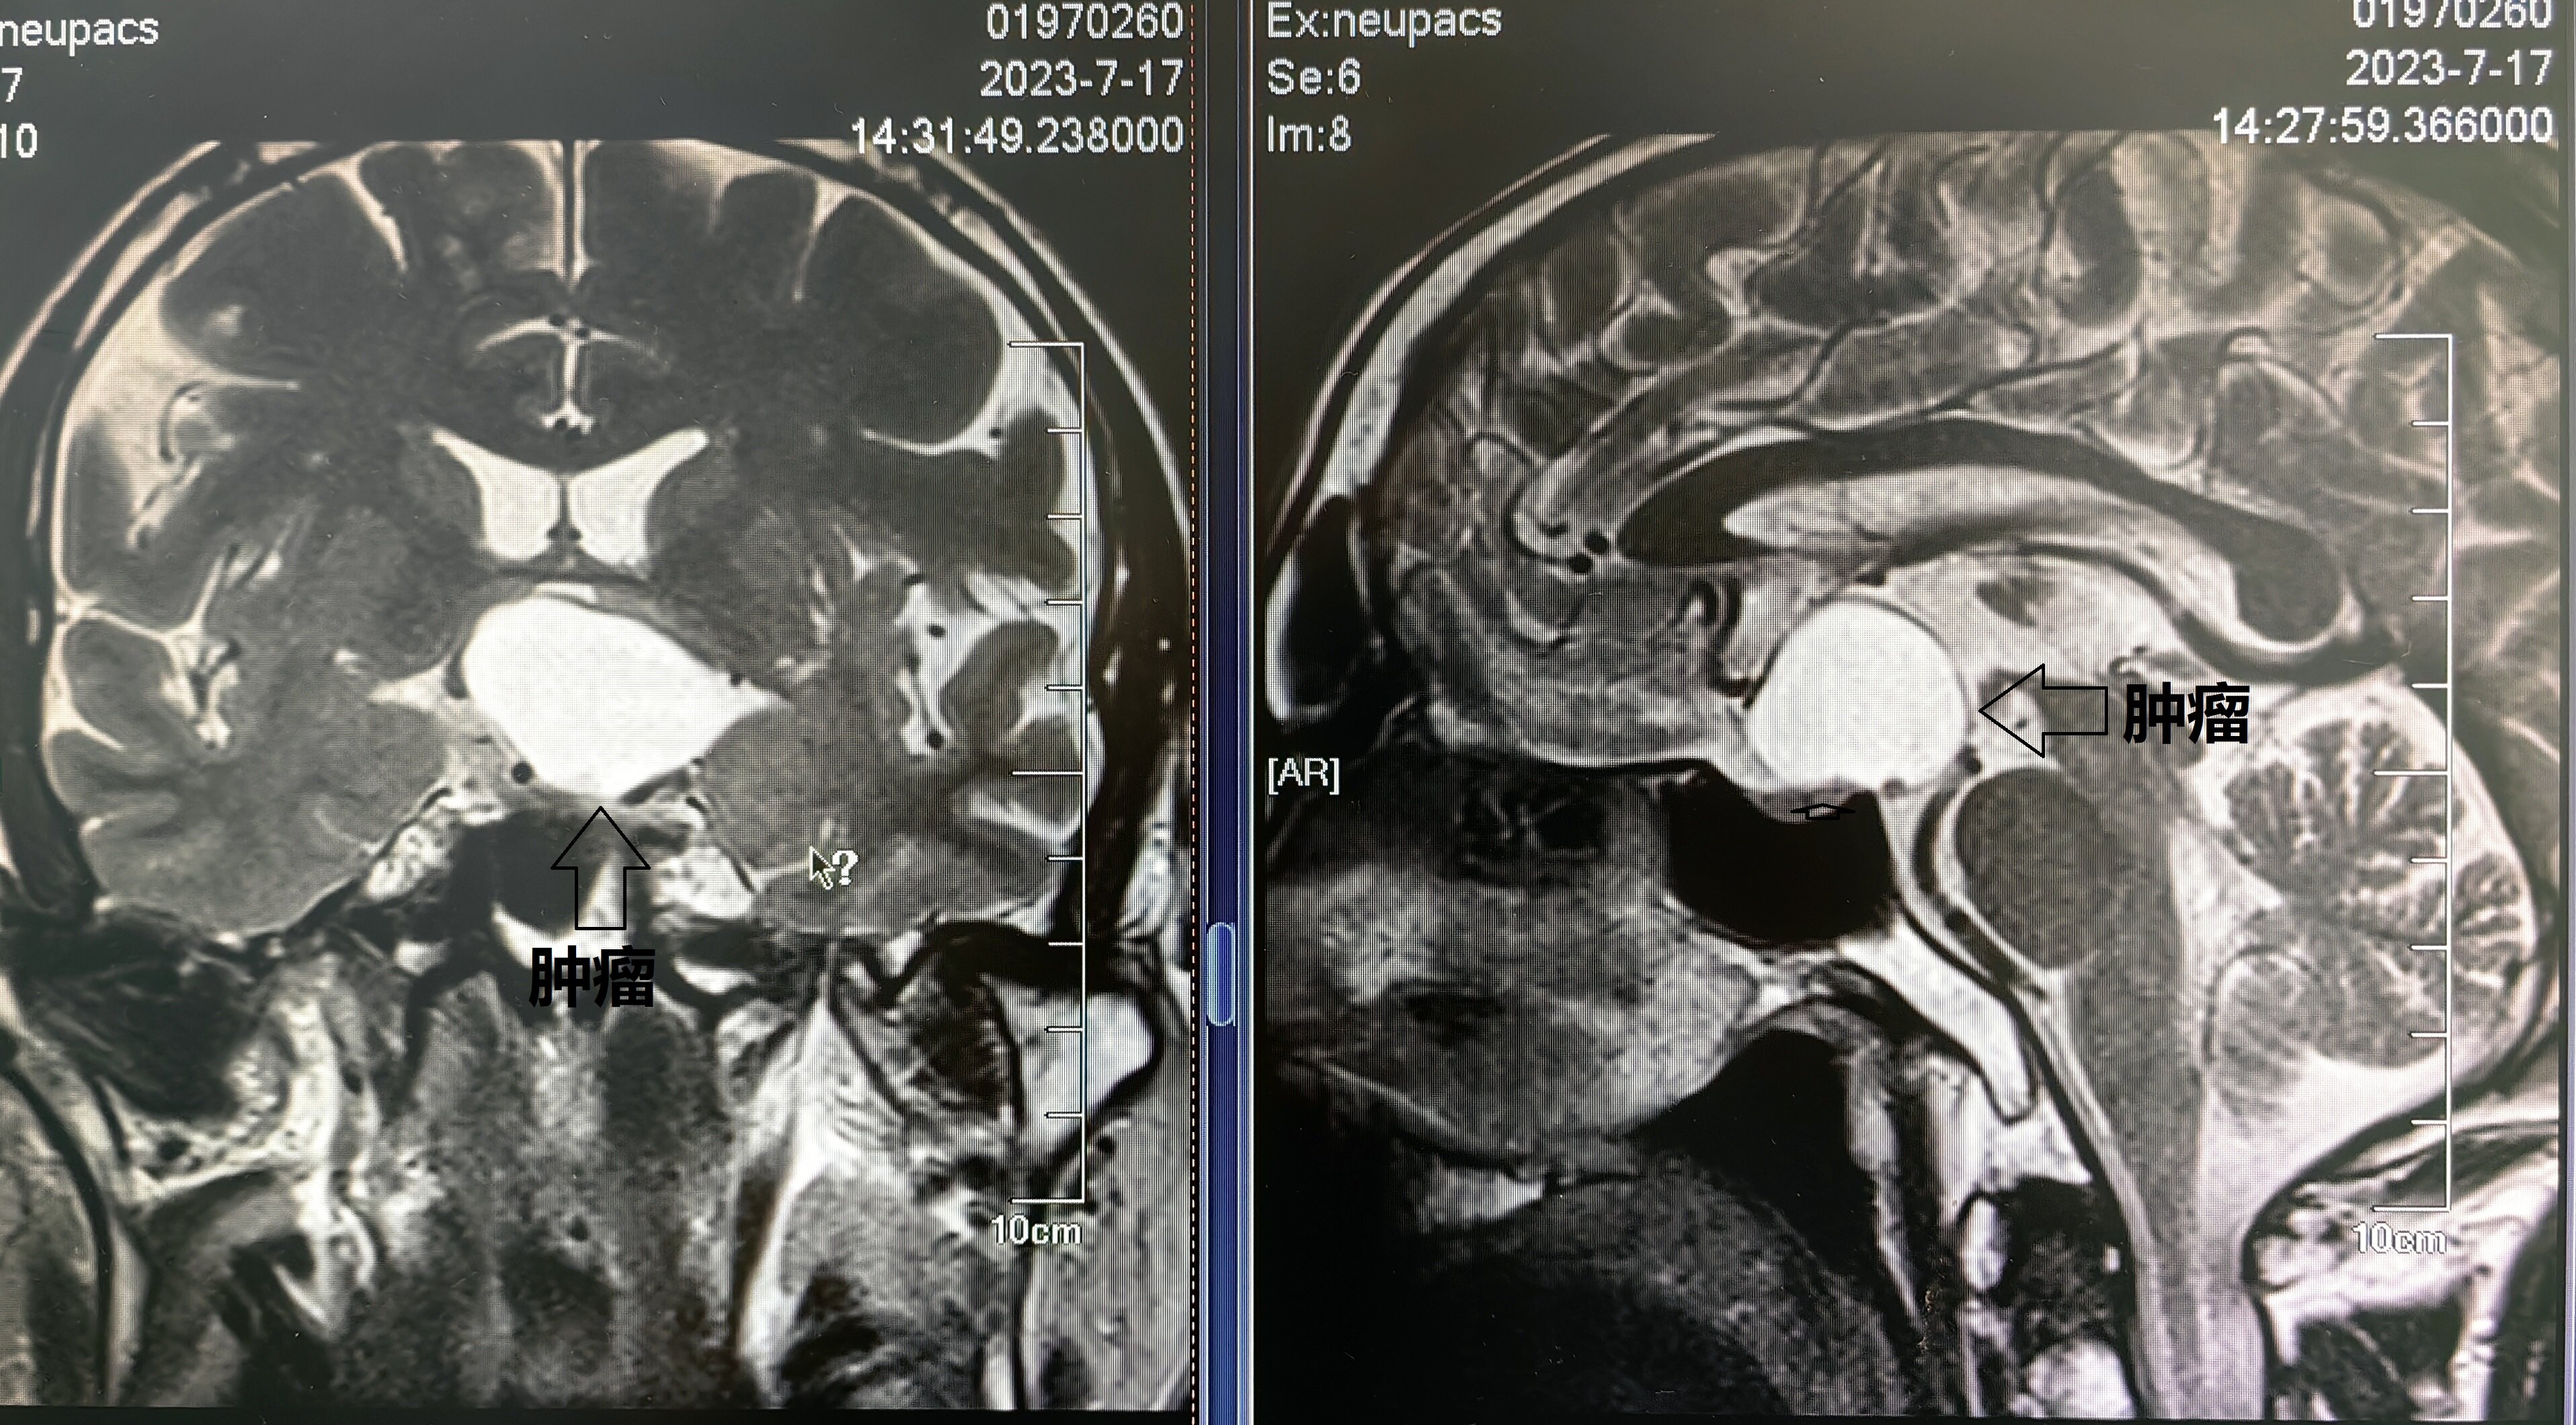

某位22歲男性患者,因?yàn)轭^痛的原因,經(jīng)過(guò)CT/MR檢查發(fā)現(xiàn)了鞍區(qū)顱咽管瘤,見(jiàn)下【圖-1】。該患者沒(méi)有視力障礙,皮膚細(xì)膩,缺乏胡須生長(zhǎng),喉結(jié)不明顯,聲音偏向女性化。醫(yī)生建議進(jìn)行手術(shù)切除,但患者及其家屬擔(dān)憂手術(shù)風(fēng)險(xiǎn),選擇了在某地進(jìn)行伽馬刀治療。之后定期復(fù)查顯示腫瘤已緩慢縮小至約一半大小,見(jiàn)下【圖-2】,但患者的女性化特征未見(jiàn)改善。醫(yī)生通常認(rèn)為,盡管顱咽管瘤在病理上被認(rèn)為是良性腫瘤,但是在臨床上通常預(yù)后不佳。當(dāng)前,手術(shù)切除仍是治療顱咽管瘤的最佳方法,伽馬刀治療作為一種輔助手段。在該病例中,直接使用伽馬刀治療并取得良好效果,為治療提供了新思路。另外顱咽管瘤還有一個(gè)重要問(wèn)題,是內(nèi)分泌功能修復(fù),但是目前還是一個(gè)巨大的難題,應(yīng)當(dāng)與內(nèi)分泌科醫(yī)師一起研討解決。某31歲患者,在三年前的體檢中發(fā)現(xiàn)鞍上區(qū)域可能存在顱咽管瘤,見(jiàn)下【圖-3、4、5】。由于沒(méi)有視力下降或其他臨床癥狀,并且擔(dān)心手術(shù)風(fēng)險(xiǎn),選擇了觀察治療。盡管半年后復(fù)查未見(jiàn)明顯變化。今年的復(fù)查顯示腫瘤已顯著增大,直徑約3cm,患者仍在考慮治療方案。顱咽管瘤的治療原則依然以手術(shù)切除為首選,尤其是在首次手術(shù)時(shí),如果能徹底切除腫瘤,大多數(shù)情況下可以達(dá)到治愈效果。在該病例中,腫瘤位于大腦中心區(qū)域,手術(shù)風(fēng)險(xiǎn)較高,保護(hù)下丘腦等重要神經(jīng)中樞和血管尤為關(guān)鍵。在治療方案的選擇上,首選手術(shù)切除的積極治療方案,其次是伽馬刀治療,因?yàn)閷?duì)于小于3cm直徑的較小腫瘤,伽馬刀治療也是一個(gè)考慮選項(xiàng)。